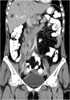

Extension of retroperitoneal mass

May Cause